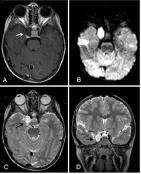

圖:海綿竇黑色素瘤,和海綿狀血管瘤容易混淆

圖:海綿竇區(qū)頸內(nèi)動脈瘤

海綿竇區(qū)表皮樣囊腫

圖:海綿竇區(qū)表皮樣囊腫